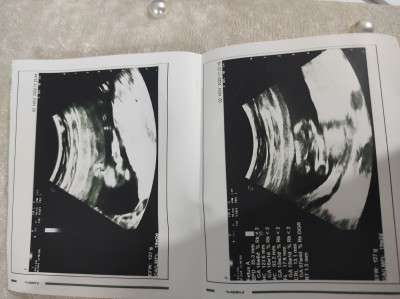

18+2 cinsiyet bilmiyoruz daha tahmin var mi acaba:((

Kız ne garip çekmiş doktor ultrason görüntüsünü

Ultrasondan anlamam daha post a girmeden kız geçti içimden hayırlısı olsun sağlıkla gelsin inşallah

Erkek yani net kağıt degil görüntü kötü cekmis ama erkek gibi

Evet devlet hastanesi çekimi

Kız biz nerden anlarız. Biliyorum diyen de uyduruyordue

Kız bebek  bacak arasi benim kızımın ultrason fotoğrafı ile aynı suan kucağımda kızım gönlüne göre ve sağlıklı al kucağına

Ee bu erkek